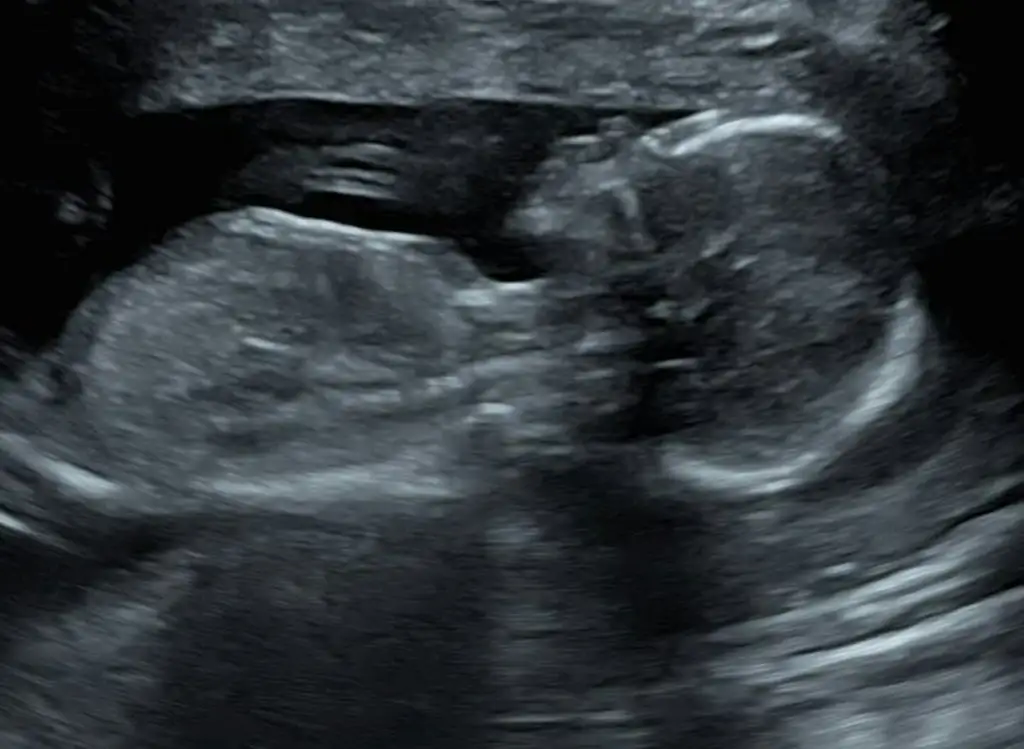

Merhaba hanımlar yeni üyeyim ilk hamileligimi yaşıyorum 16+5 haftalık hamileyim dün kontrolum vardi şükür bebeğim çok iyi ama cinsiyetini ogrenemedik doktorum bi yorumda bulunmak istemediğini tam emin olduğunda söylemek istediği söyledi eşim ve benim için öncelik tabii sağlıklı olması ama ilk olunca insan cok heyecanlı ve merakli oluyor .Bazen karın yapisindan ve ultrasondan anlayanlar oluyor tecrübeli annelerden yorum bekliyorum

Bizde daha yeni öğrenebildik :) hiç benzetme yapmadı mı Yani bana kıza benziyor dediler sonra acaba erkek mi filan dediler salı günü ayrıntılı ultrasonda netleşti.

Sizinde kız gibi sanki :))

sorma canim ya boyle oldukca daha cok heyecanlandırdi bizi bence doktorum gördü anladi ama emin olmak icin beklemek istedi diger kontrolu karnima koyunca direkt gülmeye basladi ben hemen anladim dedim noldu belli etmis mii az cok bi tahminim var ama tam acik degil bacağını koymus dedi bekledi karnimda bayağı bebek oynasin diye ama yok donmedi bebek ben simdi tam emin olmadan tahminimi soylemek istemiyorum diyodu ama gülüyor soylerken

Ben pek anlamam ama bence kız olabilirrr...

Keşke söylese :) daha çok meraklandırmak istemiş sanırım genellikle benziyor dedikleri cinsiyet çıkıyor Allah sağlık versin en önemlisi o.

Bana kız gibi geldi hayırlısı bakalım:)

Herkes kız tahmininde bulunmuş

Ama ben herkesten farklı olarak erkek diyeceğim bakalım ne çıkacak Hayırlısı olsun insAllah